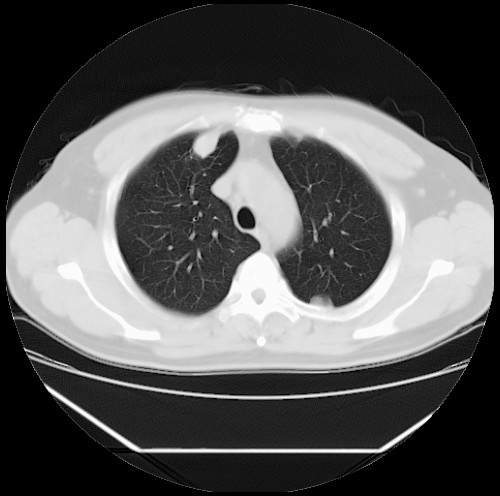

标题: CT22085:双肺多发结节

男,44岁,咳嗽,痰中带血2天。

病灶大部分位于胸膜下,结节大小相差不是很大,肺尖太干净。这种结核没见过,我认为可排除。

首先考虑转移,不除外肉芽肿、真菌感染。建议查其它。

除肺内及胸膜下可见多发大结节外,在肺小叶中心核、小叶间隔及支气管血管束上亦可见多方小结节,可以认为是随机分布。考虑转移可能性大。

仔细观察病灶形态,病灶边界部分清楚,结合临床症状,首先考虑转移,纵隔内多个肿大淋巴结影。

双肺血管纹理末端多发类圆形结节,边界光滑清晰 气管前腔静脉后淋巴结肿大

考虑转移瘤

本例双肺多发类圆形高密度灶,边清,结合病史多考虑双肺多发转移改变,可以结合实验室检查。